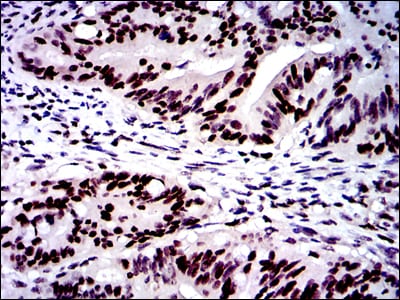

- Immunohistochemical analysis of paraffin-embedded human colon cancer tissues using MSH6 mouse mAb with DAB staining.

- Immunohistochemical analysis of paraffin-embedded human rectum cancer tissues using MSH6 mouse mAb with DAB staining.